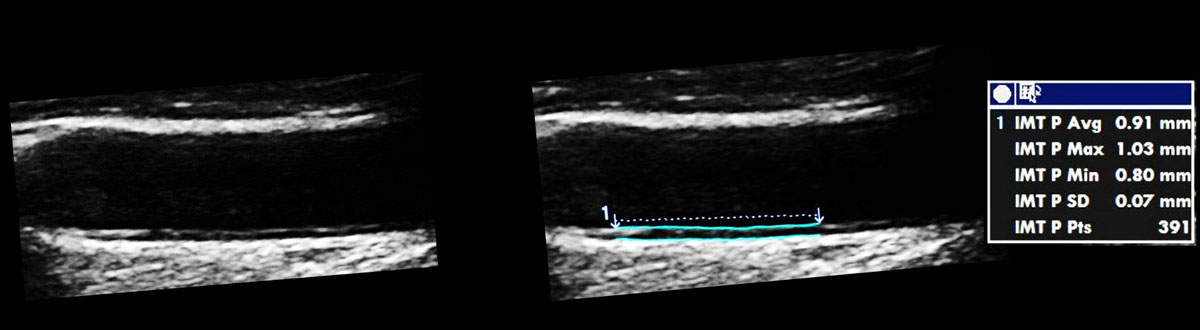

Carotid ultrasound is performed with a linear array probe (fig. 1) with a high frequency of at least 7 MHz in order to obtain sufficient resolution to image small structures [11]. The image resolution depends on the depth and the frequency used [12, 13] and is usually around 0.3 mm [14]. The anatomical region of interest is the tunica intima, which is assessed with 2D imaging without Doppler. Intima-media thickness (IMT) is the distance between the endothelium and the tunica adventitia (fig. 2). According to the Mannheim consensus, IMT is preferably measured in the far wall segment of the last 10 mm of the common carotid artery [15] (fig. 3). One major problem with carotid IMT measurements lies in the diversity of methods used, as described extensively elsewhere [16]. The variability of carotid IMT measurements is lowest in the far wall of the common carotid artery with the exclusion of carotid plaque (figs 3 and 4 ), but this increase in reproducibility goes with a loss in prediction of cardiovascular events [20, 21].

Figure 3 Intima-media thickness (IMT measurement) according to the Mannheim consensus [ 15 ]. The carotid artery IMT should be parallel to the ultrasound beam and the measurement should be performed in the distal part of the common artery using a diastolic frame and excluding carotid plaque defined by (1) thickness >1.5 mm; (2) lumen encroaching >0.5 mm; (3, 4) >50% of the surrounding IMT value. The IMT value should be derived from a length of 10 mm with 150 measures.